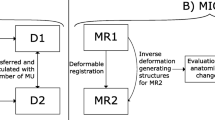

Dose reconstruction

For each treatment fraction, the 3D fractional dose distribution and the corresponding delineations were exported from the ViewRay treatment planning system. The 3D fractional dose originated from either the original non-adapted plan (in cases where the treatment was not adapted) or the adapted plan (153/174 fractions were adapted). For interrupted fractions, the dose distributions from sub-fractions were merged, together with the prostate motion extracted from the separate cine MRI data series. All sub-fractions shared the same segmentation.

Since it was not possible to have access to the linac or multileaf collimator log files, a time-resolved segment-by-segment dose reconstruction could not be implemented. As an approximation for reconstructing the delivered dose, the static dose cloud approach was used [31, 32]. The static 3D fractional dose distribution was shifted rigidly with the inverse of the gated 2D prostate motion vectors extracted from the 2D cine MRI. The shifted dose distributions were averaged to estimate the delivered fractional dose, labelled gated dose. To reconstruct the dose of a hypothetical non-gated delivery, the same approach was adopted using the non-gated motion.